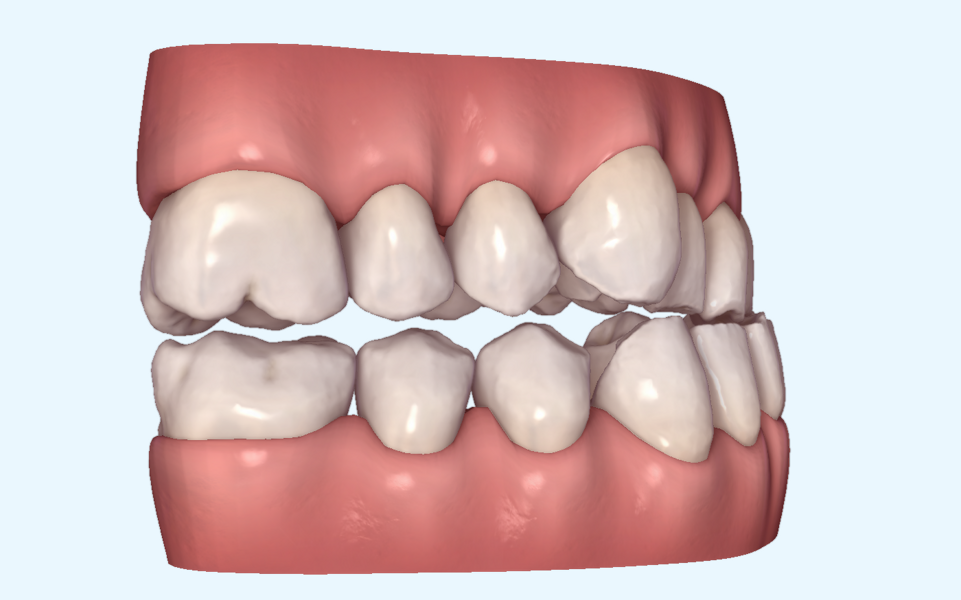

This patient, like all patients requiring interdisciplinary rehabilitation, had to first undergo periodontal treatment and caries restoration (Fig. 17). At the same time, it was important to rehabilitate swallowing with Froggymouth and relax the masticatory muscles and relieve the TMJs with an occlusal device. We could then study the orthodontic treatment plan using Invisalign ClinCheck (Align Technology) and showed the treatment plan to the interdisciplinary team and to the patient (Fig. 18). We were then able to create the correct sequence of orthodontic treatment, bone augmentation and implant surgery needed for the posterior edentulous spaces.

After the first phase of aligner treatment, we had achieved better inter-arch coherence, better maxillary arch expansion, and some space for improving the anterior tooth proportions restoratively (Fig. 19). We then temporarily restored the anterior teeth directly with composite, closing the spaces, improving the tooth proportions and further increasing the maxillary arch expansion (Fig. 20). We used restorative arch expansion to reduce the orthodontic destabilisation of the teeth to achieve the correct inter-arch coherence and retain the teeth in the cortical bone.38 A refinement aligner phase was undertaken to improve the final alignment of the gingival zenith and to improve the inter-arch coherence (Fig. 21). The periods of the first orthodontic phase and of the refinement were used to augment the mandibular and maxillary bone and to place the implants (Fig. 22). At the end of the orthodontic treatment, the case was finalised with ceramic veneers in the anterior area and temporary restorations on the implants in the posterior area (Figs. 23–26).